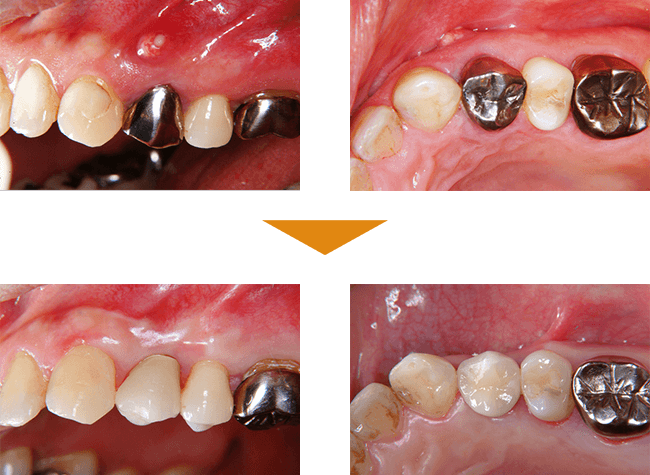

症例1

単独歯 インプラント即時荷重

| 治療期間 | 約4カ月 |

| 費用 |

インプラント治療費 400,000円

造骨費用 50,000円

合計 450,000円(税込) |

※状態により、骨補填等別途で費用が発生する場合もございます。

症例2

単独歯 インプラント即時荷重

| 治療期間 | 約4カ月 |

| 費用 | インプラント治療費 400,000円

造骨費用 50,000円

合計 450,000円(税込) |

※状態により、骨補填等別途で費用が発生する場合もございます。